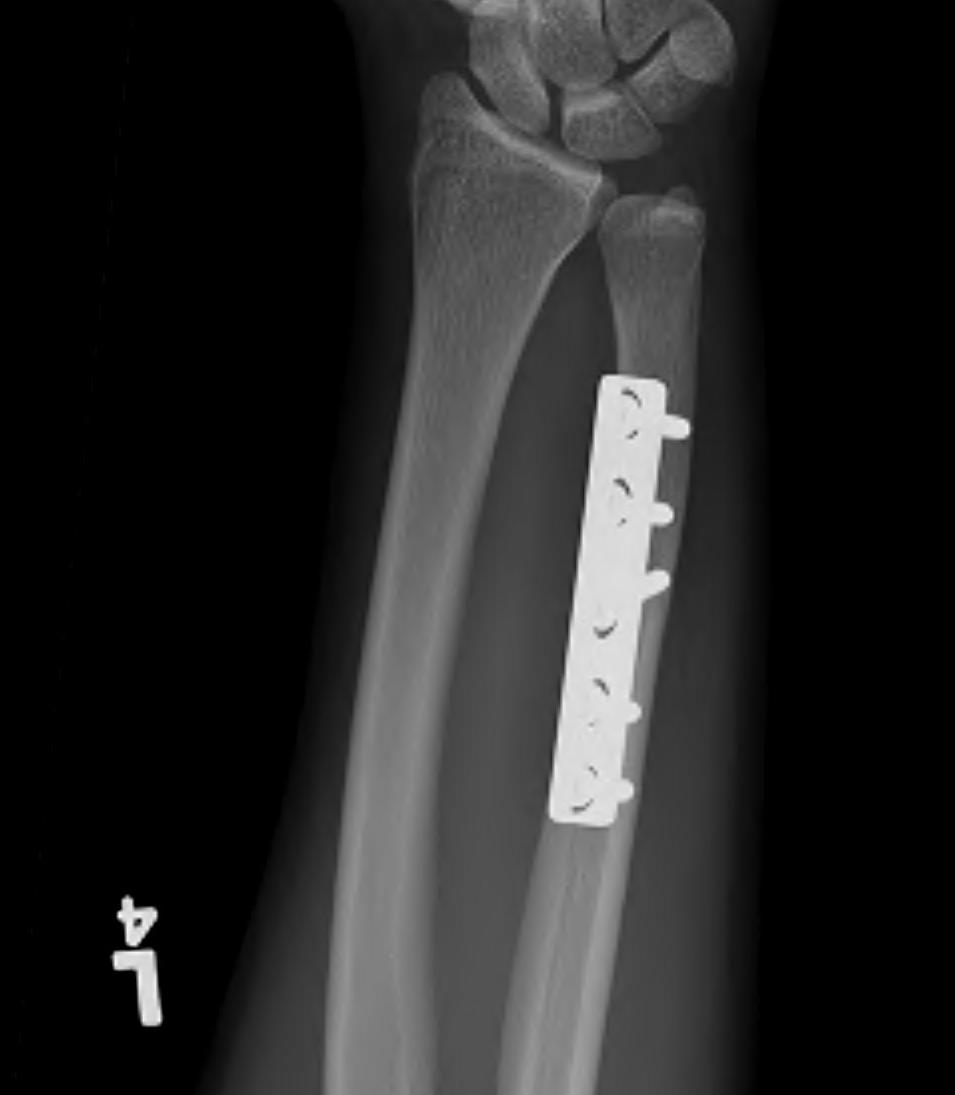

Ulna shortening osteotomy

Technique

Approach to ulna

- between ECU and FCU

- can use cutting jigs

- resect 2 - 6 mm of ulna based on xray templating

- compression plate